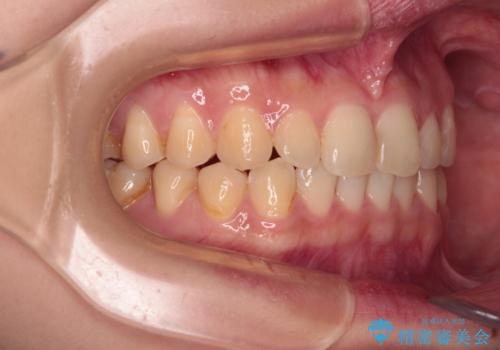

治療途中の奥歯と矯正治療の後戻り インビザライン・ライトによる矯正治療

- 根管治療を行ったままの奥歯と、矯正治療の後戻りを気にして来院された患者様です。

根管治療された歯に症状はなく、オールセラミッククラウンにて補綴治療を行うこととしました。

矯正治療の後戻りは軽微であったため、インビザラインの簡易パッケージであるインビザライン・ライトを用いて歯列を整えることとしました。

クラウンはよりよい咬み合わせで装着したいため、インビザラインを1セット使用して概ね歯列を整えた時点で補綴治療を行い、その後仕上げの矯正治療を行いました。